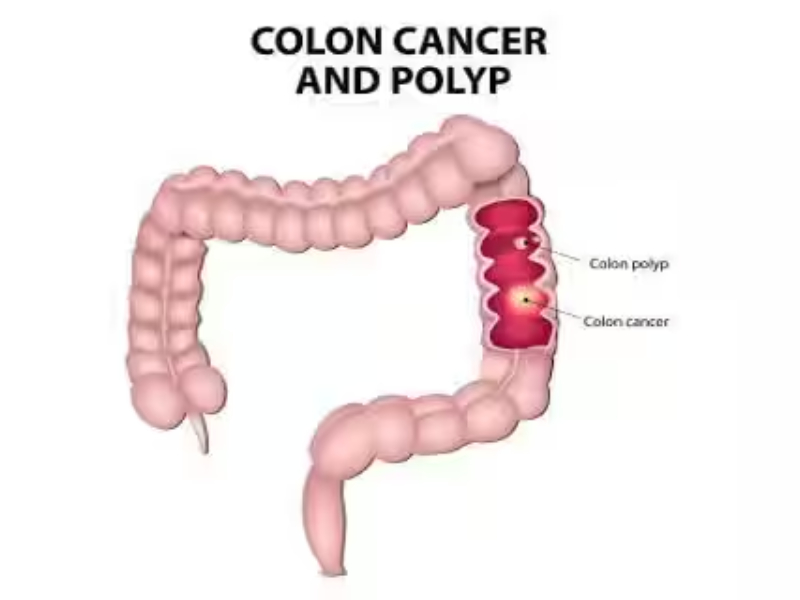

Tumors & Cancers

Discover symptoms & explore medicines and treatment options. Also read expert health articles about symptoms, the latest research, medicines and alternative treatments for every disease and medical condition.